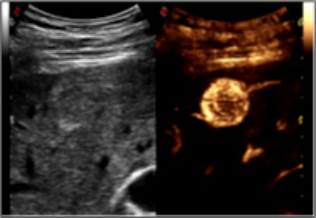

微血管“珊瑚”成像 (MicroV):

采用百胜专利计算方式,在有效保证帧频的前提下,去除背景噪声,降低周边 强回声结构信息干扰,保证清晰可视细小血管和低速血流。具有 5 种成像方式,可 应用于各类探头的不同临床应用。对于无创、快速的检测极低速血流成像有明显帮助, 可应用于:小血管、风湿、脑血管疾病诊断

造影谐波成像(Ultra-CnTI):

通过对发射脉冲频带及能量的精确控制,使脉冲能够最佳匹配造影剂微泡的非 线性响应,从而获得纯净、丰富的、超强的造影剂回波信号。